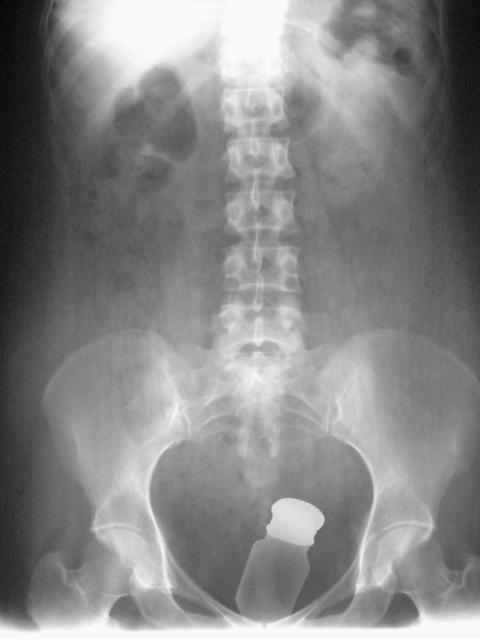

La edición norteamericana de' Cosmopolitan' ha elaborado un lista con los objetos más extraños extraídos de los rectos de diferentes personas. Desde llaves, linternas o gafas de sol, cualquier objeto es bueno para pasar un agradable momento debieron pensar estos 'viciosos' pacientes.